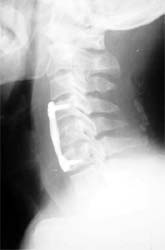

颈椎5骨折,椎体及间盘压迫硬膜囊,患者高位截瘫

前路减压,椎间植骨,钢板内固定,同期进行后路减压手术。 截瘫部分恢复,生活自理。